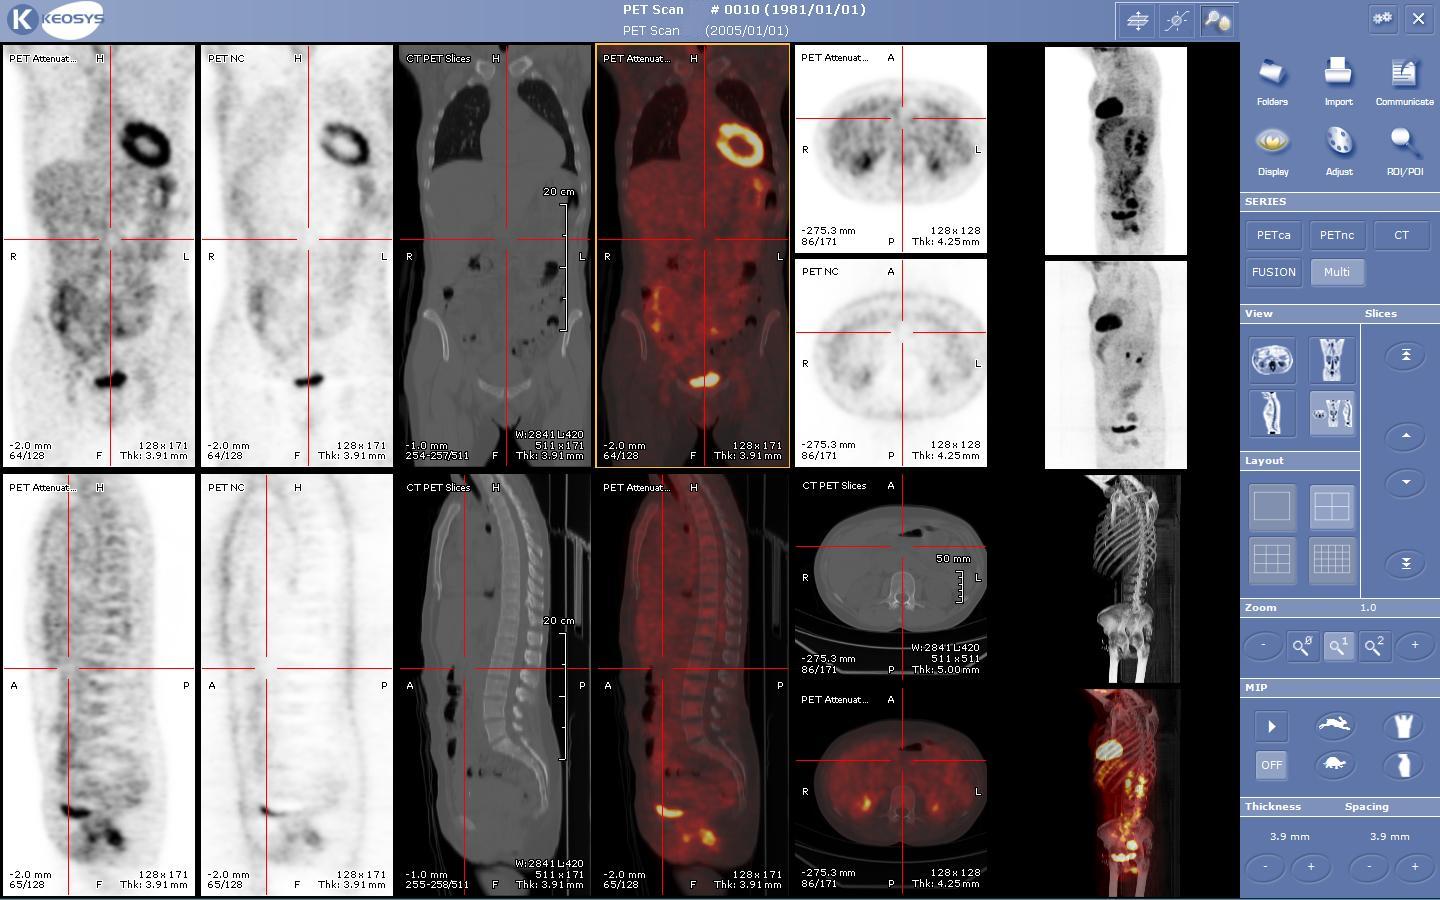

5. PET-CT 및 PET-MRI

PET-CT는 PET와 CT를 결합한 장비로, 해부학적 정보와 대사 정보를 함께 얻을 수 있어 유용하다. 최신 PET 스캐너는 고급 멀티 검출기 배열 CT 스캐너와 통합되어 제공되며(PET-CT), 동일한 세션에서 두 스캔을 순차적으로 수행할 수 있다. 환자는 위치를 변경하지 않아도 되므로 두 영상이 정확하게 등록되어, PET 영상의 이상 부위가 CT 영상의 해부학적 구조와 더욱 완벽하게 연관된다. 이는 움직이는 장기나 구조의 상세한 뷰를 보여주는 데 매우 유용하다.

CT나 MRI가 주로 조직의 형태를 관찰하는 검사인 반면, PET는 SPECT 등 다른 핵의학 검사와 마찬가지로 생체의 기능을 관찰하는 데 특화된 검사법이다. 암 진단에 이용되기도 한다. 환자에 대한 피폭량은 CT에 비해 적지만, 의료진의 피폭량에 주의가 필요하다. PET/CT 장치를 이용한 검사의 경우 피폭량이 CT에 비해 커지는 경우가 있다.

CT와 PET를 비교하면, CT에서는 외부에서 X선을 조사하여 전체적인 모습을 관찰하는 데 반해, PET 등의 핵의학 검사에서는 생체 내부의 방사성 추적자를 관찰한다는 차이가 있다. CT 영상은 해부학적인 정보에 뛰어나므로 형태 영상이라고 불리고, PET 영상은 생리학적인 정보에 뛰어나므로 기능 영상(functional image)이라고 불린다. PET와 CT를 일체화한 PET-CT 장치를 이용한 검사의 경우, 1회 검사에서의 방사선 피폭은 23–26 mSv가 된다 (체중 70 kg 기준)[100]。이에 비해, 방사선 진료에서의 대표적인 X선 검사에서의 피폭량은, 흉부 0.04mSv, 복부 1.2mSv, 상부 소화관 8.7mSv, 흉부 CT 7.8mSv, 복부 CT 7.6mSv이다[101]。일본에서는, 인체는 자연계로부터 연간 2.1mSv 전후의 피폭을 받고 있다 (2011년 추정)[102]。